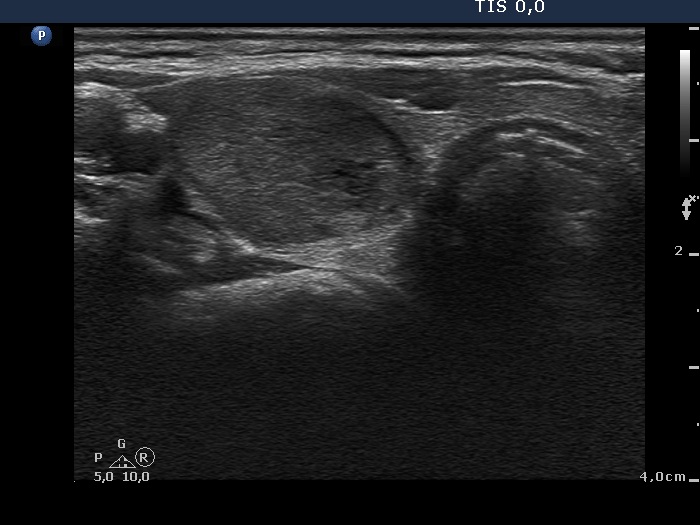

Ultrasonography. There was a moderately hypoechogenic nodule presenting halo sign and perinodular blood flow in the right while two smaller lesions in the left lobe. One of the latter displayed multiple microcalcifications.

The mass in the left side of the neck corresponded to a conglomerate of multiple lymph nodes. These were irregular in shape and presented cystic and necrotic areas. There was no hilum present. The lymph nodes were avascular.